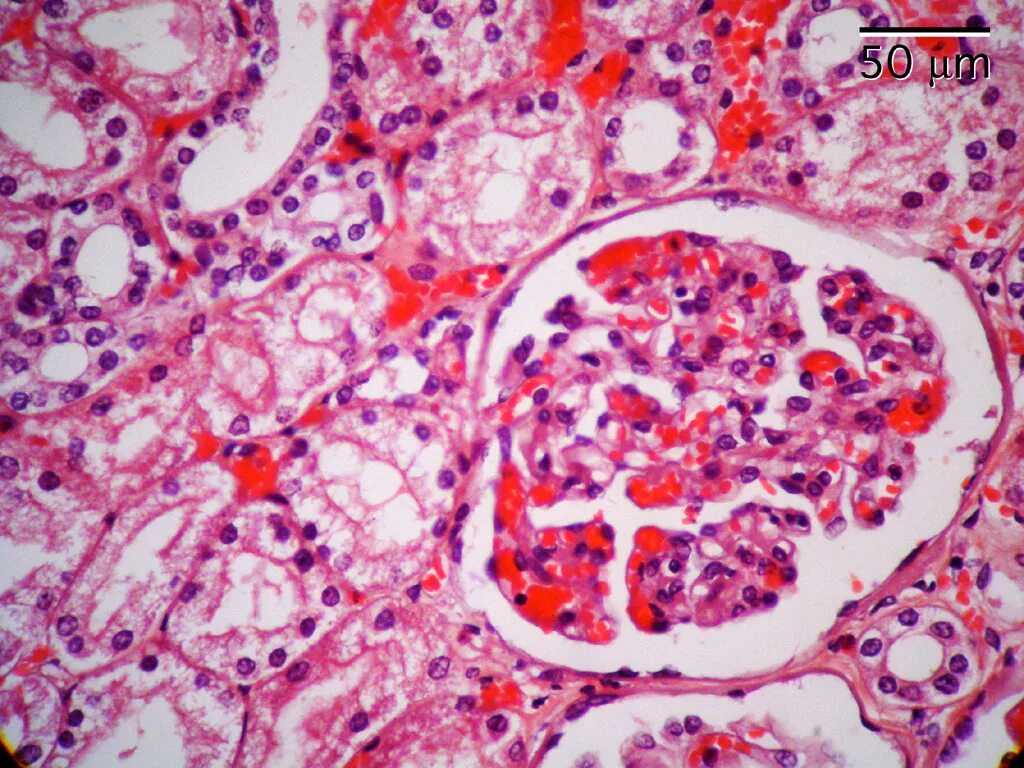

Гистологическое исследование почек